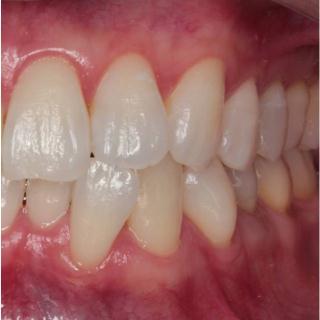

歯並びは正常な位置に生え揃うことが理想的ですが、さまざまな原因で下のように歯並びが乱れてしまう場合もあります。

矯正歯科の目的は、歯並びをゆっくりと美しく治し、心身が健康になることです。

矯正治療は長期にわたるために、治療に関するどんなことでも気軽に話し合いながら、丁寧にコミュニケーションをとりながら、正しい歯並びへと治療を進めてまいります。

矯正装置は種類も数多くありますが、当院では患者様の現在の状態やコスト面などにも考慮して、最適な治療計画を提示しながら治療を提供しています。